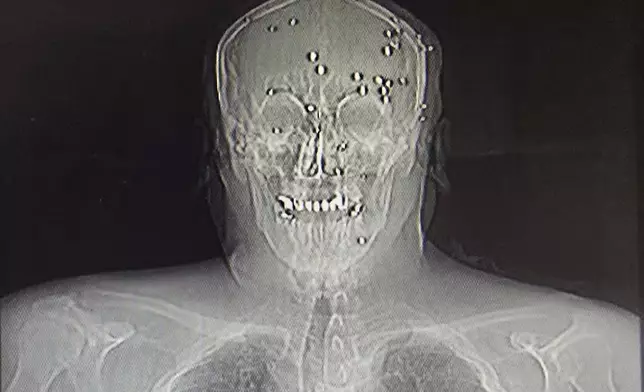

This is a photo of an X-ray image taken Jan. 9, 2026, obtained outside Iran, showing an Iranian protester who was hit in the face by pellets in Rasht, northern Iran. (UGC via AP)